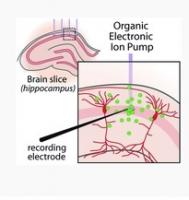

ÉPILEPSIE: La pompe ionique qui éteint la crise au niveau du pixel neuronal

Actualité publiée le 25/08/2016PARKINSON: Inhiber une enzyme pour ralentir la maladie